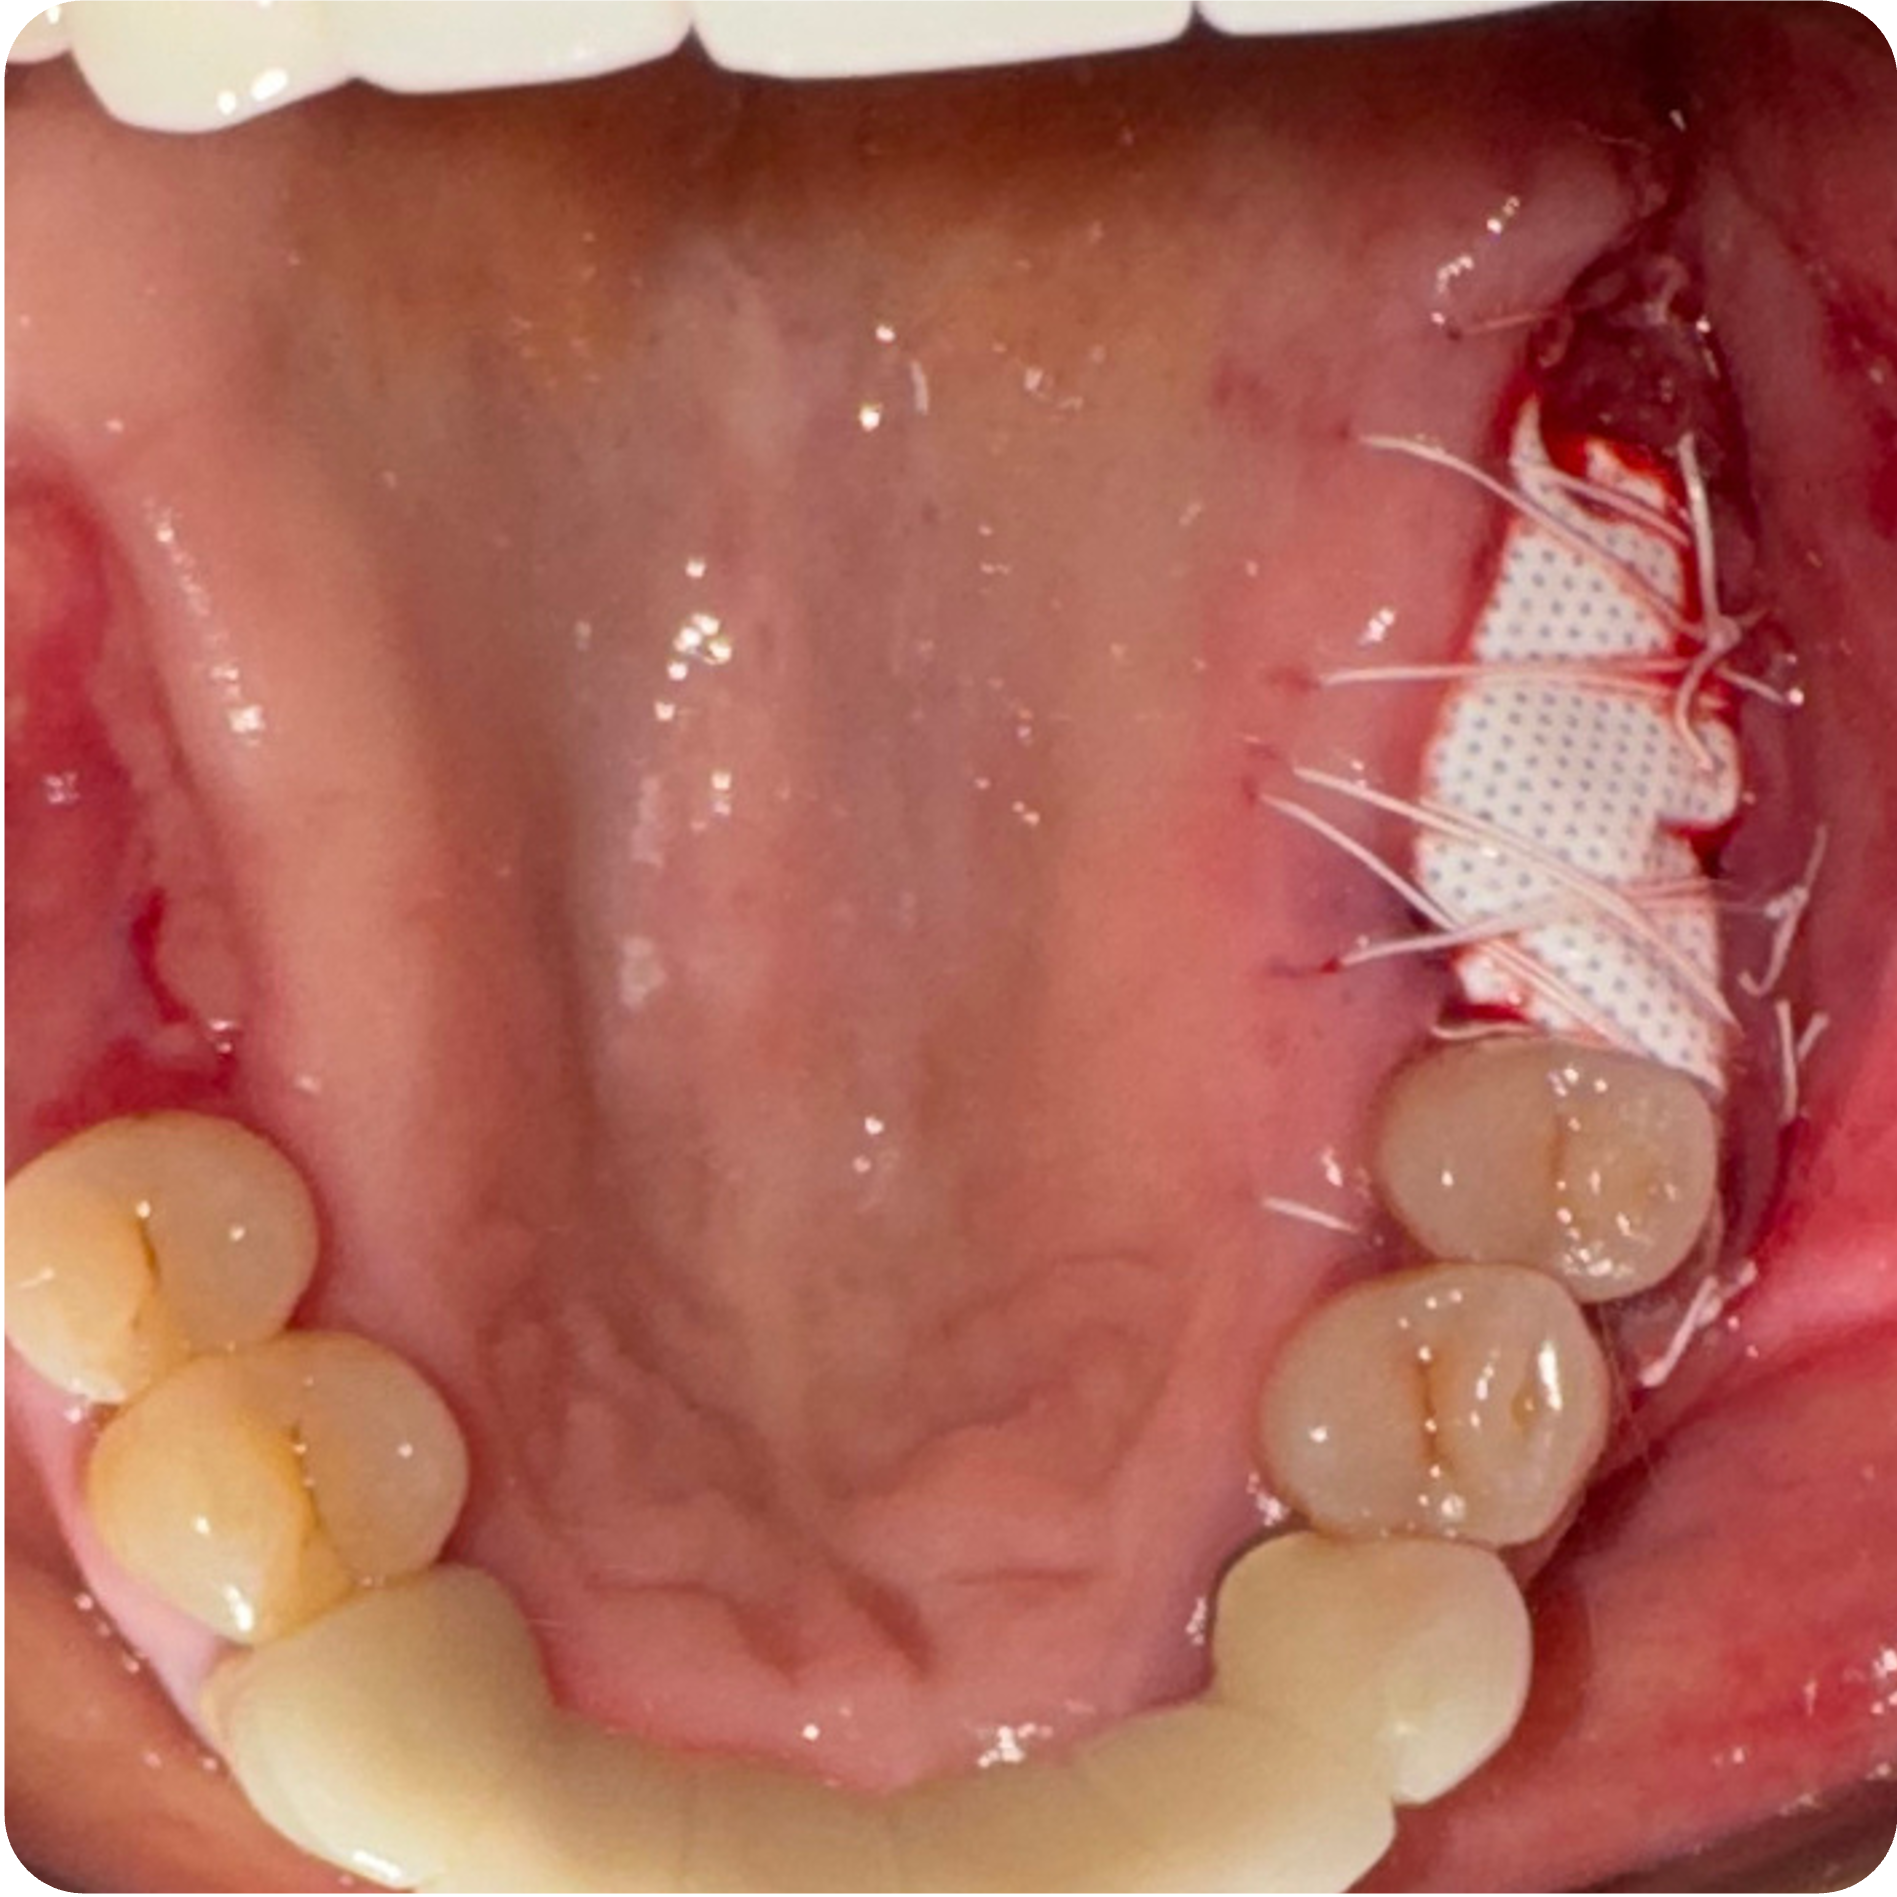

May 22, 2025Extractions with bone grafting (#2, #3, #30, #31) + Covered Socket Residuum (CSR) ~ Previously known as cavitation ~ protocols (#1 and #32) with protection protocol (lower right & upper right).

June 12, 2025Membrane removal for #2, #3, #30, and #31 surgical sites.

Visual Case Progression

All clinical images are shown at a consistent size for easy comparison.

- Guided Open Wound Healing Protocol (GOWH): Extractions and Covered Socket Residuum (CSR) ~ Previously known as cavitation ~ sites were treated following the Guided Open Wound Healing Protocol developed by Professor Shahram Ghanaati, MD, DDS, PhD. This protocol focuses on thorough debridement, biological tissue management, and optimized healing conditions to support predictable bone regeneration and reduce inflammatory burden.

- Staged Extractions with Guided Bone Regeneration: Compromised teeth were removed atraumatically and grafted to preserve bone volume and create stable foundations for future implants.